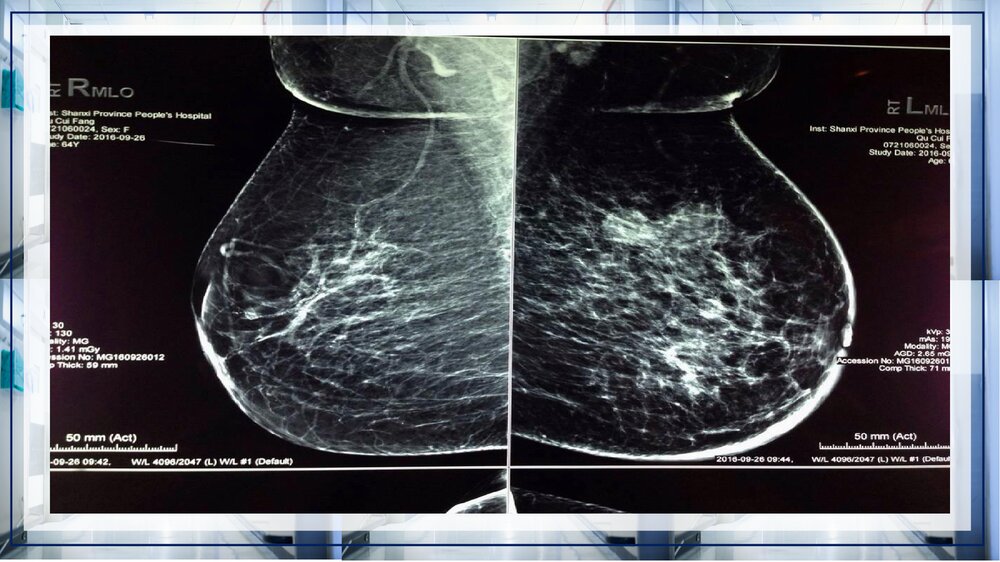

关于乳腺癌病例讨论关于乳腺癌病例讨论XXX:凡心20XX年X月XX日病史女性,52岁,发病急。发现左乳皮肤红肿2个月。患者入院前2月余,无意间发现左乳皮肤红肿,偶有乳房疼痛,门诊手诊可触及左乳外上片状增厚区,乳腺钼靶示左乳多发结节,BIRADS4b,右乳未见异常。既往史1998年因子宫肌瘤行子宫全切术;高血压病史17年,平素口服尼群地平、硝酸异山梨酯,自诉血压控制可;糖尿病病史15年,平素口服二甲双胍、格列本脲,自诉血糖控制可。专科检查双乳外形不对称,左乳明显增大,双乳头无内陷及偏移,左乳外上方可触及片状增厚区,范围约3.5*3㎝²,质硬,边界不清,活动度尚可,无压痛。左乳下方可见橘皮征,范围约20*22㎝,局部皮肤略红,皮温增高,右乳正常。左腋下可触及一肿大淋巴结,大小约1*1.5㎝²...